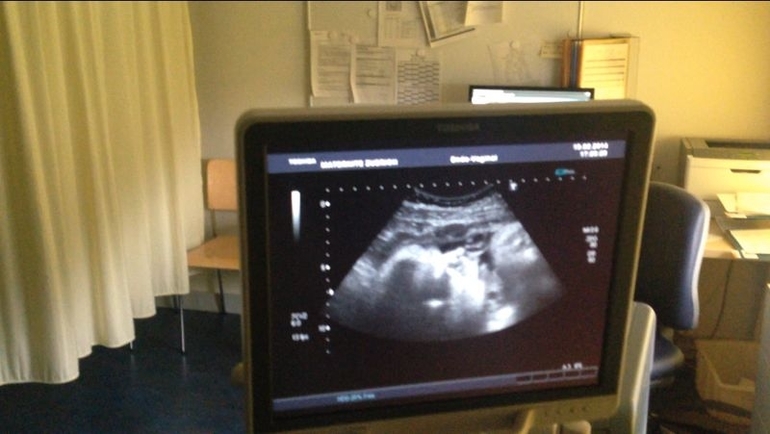

наши портретные Узи в конце 38-ой недели

Малыш, до и после родовНаши новые фоточки с Узи на 38 неделе,личико сильно изменилось

Предидущие фоты для сравнения на на 28-ой неделе

и на 32-ой неделе